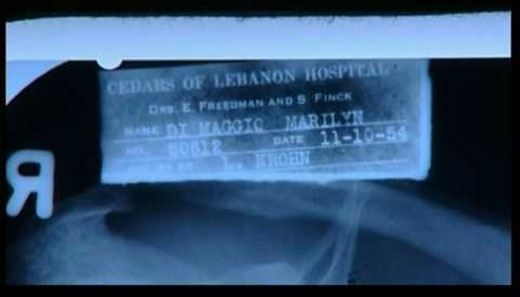

Radiografías de Marilyn Monroe, bajo el nombre de Marilyn DiMaggio, sacadas por un joven médico en 1954.